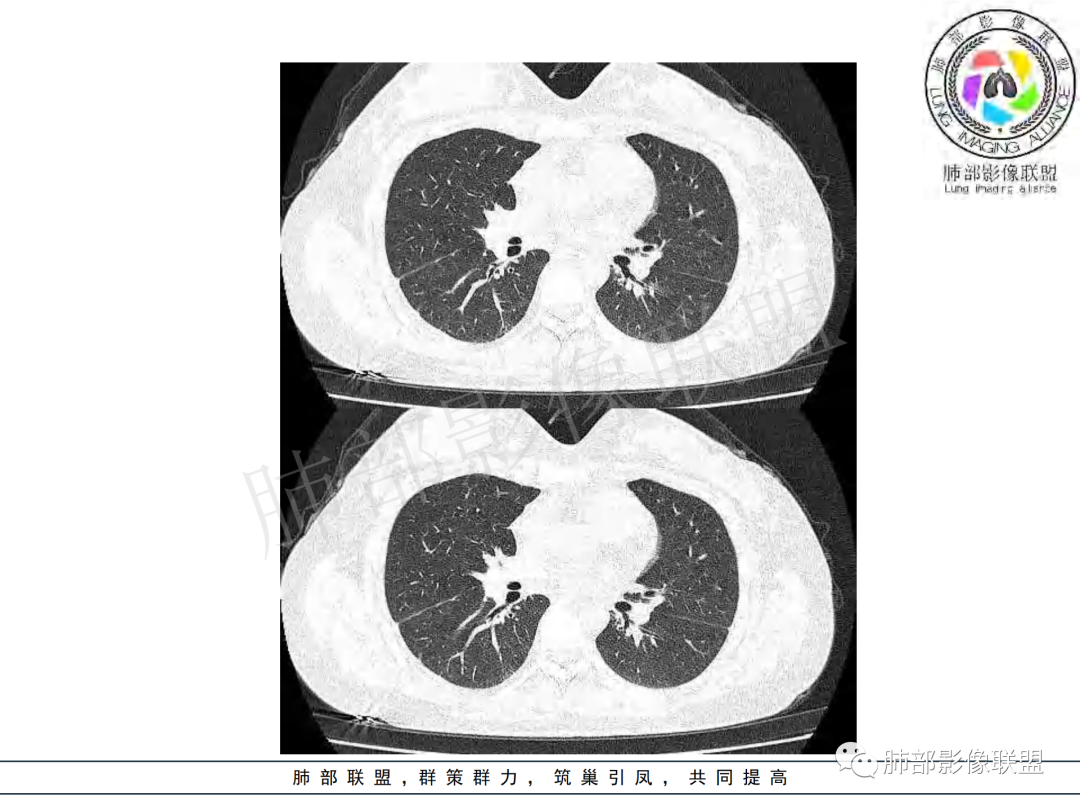

右肺肺门旁肿块,右肺中间段支气管腔内结节,增强强化不均;纵隔多发淋巴结环形强化,右侧少量胸腔积液,临床发热入院,考虑结核,鉴别肿瘤。

右肺门增大,远端花花草草不明显,支气管管壁增厚,纵隔淋巴结环形强化,年龄,病程,考虑炎性病变,结核可能,有个层面支气管截断,有强化,鉴别粘表。

女,20,病程长达8月,发热、胸痛、右侧胸腔积液病史。胸部CT:右肺门旁不规则肿块影,右中间支气管腔内结节,纵隔多发淋巴结肿大;强化不均匀,灶性坏死灶,环形强化;右侧少量胸腔积液并局部肉芽肿样突起。年轻女性,长病程,多部位,考虑慢性炎症,结核?鉴别肿瘤。

青年,右肺门增大,见软组织肿块影,部分支气管腔结节,并管腔狭窄,增强后明显不均匀强化,伴纵隔多发肿大淋巴结,环形强化,考虑恶性,类癌,鉴别支气管内膜结核

右肺门不规则肿块,向气管腔内生长,不均匀强化,其内粘液栓,纵隔淋巴结增大,部分有坏死,胸膜结节强化,考虑恶性,粘表?类癌?鉴别结核

右肺肺门旁肿块,右肺中间段支气管腔内结节,增强强化不均;纵隔多发淋巴结环形强化,右侧少量胸腔积液,考虑结核可能,鉴别肿瘤。

年轻女性,慢性病程,发热、胸痛。右肺门旁不规则肿块影,纵隔多发淋巴结肿大;强化不均匀,环形强化;右侧少量胸腔积液;首先考虑结核,鉴别肿瘤,结节病。

年龄和病史比较符合结核,但是中叶支气管好像堵塞了,管腔有新生物,恶性肿瘤也不能排除,做一个支气管镜应该能确诊

年轻女性 大支气管占位恶性三件套 高强化 内部可见无强化区,无强化区与强化区内边界大部分不清晰,类癌、粘表、腺样囊性癌。首先考虑粘表   其次需要鉴别的有结核   这么大片的坏死 结节病可能性小

青年女性,发热、胸痛、右侧胸腔积液病史,病程8个月。曾多次抗炎后均有好转。CT:右肺门旁肿块影,双侧胸膜结节,纵隔多发淋巴结肿大,边缘模糊;增强渐进性明显强化,纵膈淋巴结较彻底坏死灶,边缘环形强化。考虑结核,鉴别恶性肿瘤。

女性,20岁。高热、畏寒。右肺上叶近肺门区不规则肿块,周围斑点、片小结节影伴肿大淋巴结,肿块包绕并突入右主支气管腔内,增强后肿块不均匀强化,淋巴结环形强化中心低密度,考虑结核。

纵隔肺门及两侧胸膜强化结节,支气管管腔不通畅。结核能解释临床及影像,就是强化有点猛,这个妖怪真不好说。恶性如类癌/高级别黏表/恶性间皮也要考虑。

本例患者,年轻女性,慢性病程,多次抗感染治疗效果不佳,实验室检查示白细胞及中性粒细胞不高,不支持普通细菌感染,虽然肺泡灌洗液X-Pert检测阴性,结合患者胸部CT结核感染亦不能排除,胸部CT主要表现为右侧肺门及纵隔淋巴结肿大,仔细观察不难发现右中间支气管内新生物凸向管腔内,增强扫描,右肺门(10R)及纵隔淋巴结(2R,4R)明显不均匀强化,内部呈不规则低密度无强化区,被周边高强化区包绕(环形强化)的特点,首先应当想到纵隔淋巴结结核诊断。淋巴结分布亦不符合肺部恶性肿瘤迁徙途径。